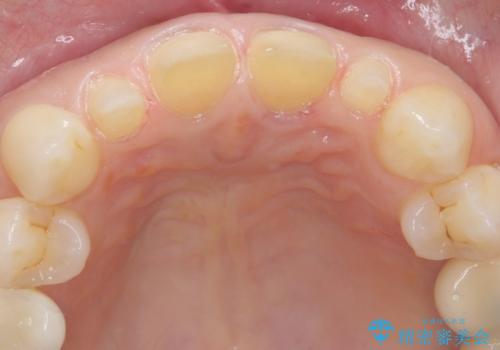

- 前歯が大きいのを揃えたいとのことでした。

少し削って長さを短くして様子を見ましたが、どうしても気になるとのことでした。

隣の前歯が小さいため、4本被せてバランスをとりました。